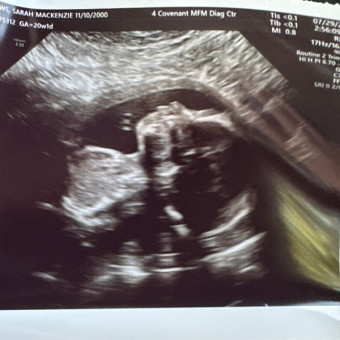

Rylee’s Baby Registry

Sarah & Cody Andrews

Lubbock, TX

December 15, 2025